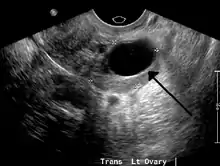

Ovarian cysts are usually diagnosed by ultrasound, CT scan, or MRI, and correlated with clinical presentation and endocrinologic tests as appropriate.[10]

Ultrasound

Follow-up imaging in women of reproductive age for incidentally discovered simple cysts on ultrasound is not needed until 5 cm, as these are usually normal ovarian follicles. Simple cysts 5 to 7 cm in premenopausal females should be followed yearly. Simple cysts larger than 7 cm require further imaging with MRI or surgical assessment. Because they are large, they cannot be reliably assessed by ultrasound alone; it can be difficult to see posterior wall soft tissue nodularity or thickened septation due to limited ultrasound beam penetrance at this size and depth. For the corpus luteum, a dominant ovulating follicle that typically appears as a cyst with circumferentially thickened walls and crenulated inner margins, follow up is not needed if the cyst is less than 3 cm in diameter. In postmenopausal patients, any simple cyst greater than 1 cm but less than 7 cm needs yearly follow-up, while those greater than 7 cm need MRI or surgical evaluation, similar to reproductive age females.[11]